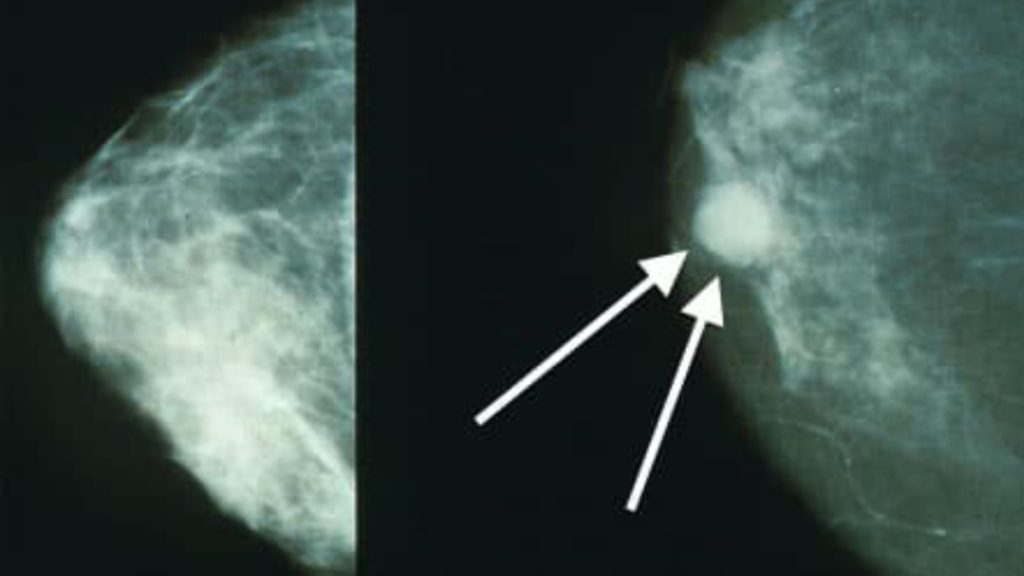

عکس ماموگرافی مشکوک

در گزارش رادیولوژی، یک عکس زمانی “مشکوک” تلقی میشود که در سیستم نمرهدهی BIRADS نمره ۴ یا ۵ بگیرد. نشانههای بصری مشکوک در عکس عبارتند از:

- تودههایی با لبههای نامنظم یا ستارهای شکل (که به بافت اطراف چنگ انداختهاند).

- تجمع ریزدانههای کلسیم (نقاط سفید بسیار ریز) در یک منطقه خاص.

- عدم تقارن بافتی که در عکس سینه دیگر دیده نمیشود.

- بهم ریختگی ساختار بافت سینه (Architectural Distortion).

نکته مهم: مشکوک بودن به معنی قطعی بودن سرطان نیست، بلکه یعنی نیاز به نمونهبرداری (بیوپسی) وجود دارد.

عکس ماموگرافی سرطانی

تصاویر بدخیم معمولاً ویژگیهای خاصی دارند که رادیولوژیست را نگران میکند:

- تودههای اسپیکوله (Spiculated): تودهای که شبیه خورشید اشعههایی به اطراف دارد.

- میکروکلسیفیکاسیونهای پلئومورفیک: رسوبات کلسیمی با اشکال و اندازههای مختلف که در یک جا جمع شدهاند.

- کشیدگی پوست یا نوک سینه: در عکس دیده میشود که بافت سینه ضخیم شده یا به سمت داخل جمع شده است.

این علائم در ماموگرافی دیجیتال با وضوح بسیار بالایی قابل تشخیص هستند.